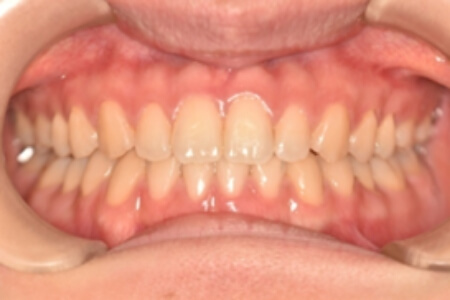

すきっ歯・正中隔離(非抜歯)【0625】

初診時

治療内容の詳細 初診時21歳の女性で、上顎前歯部の隙間(正中離開)を主訴として来院されました。

検査の結果、上下顎前歯部に空隙を伴うアングルⅠ級不正咬合と診断しました。

治療としては、非抜歯の上、マウスピース矯正装置(インビザライン)で配列を行いました。